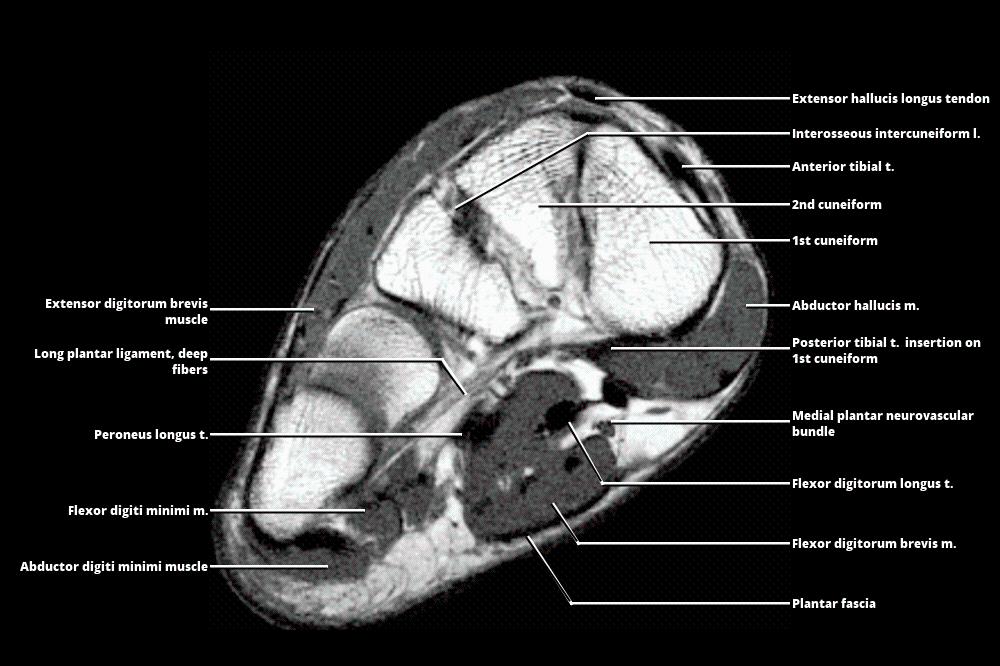

Foot Muscles Mri : Anatomy Of The Foot And Ankle - MRI / A Magnetic

serialkeyadobecs3prem86476.blogspot.com

serialkeyadobecs3prem86476.blogspot.com

MRI - FOOT

www.wangmd.com

www.wangmd.com

mri atlas

MRI - FOOT

www.wangmd.com

www.wangmd.com

mri

MRI - FOOT

www.wangmd.com

www.wangmd.com

mri

Mri atlas. Foot muscles mri. Mri plantar axial nerve lateral t1 ankle medial weighted brevis flexor entrapment mpn trescot md digitorum calf intrinsic ligament fasciitis